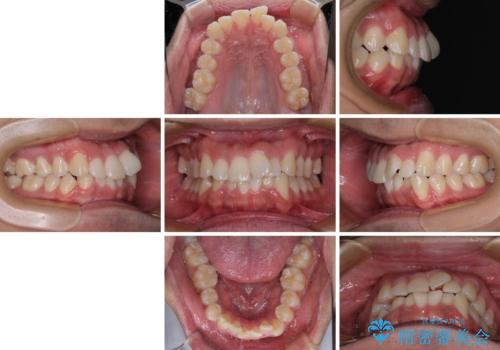

- 前歯のデコボコを治したいとのことで来院された患者様です。

上下顎ともに歯列全体の後方移動とIPR(歯と歯の間を削る)によってデコボコが解消するように設計し、インビザラインにより治療を行うこととしました。

下顎前歯は後戻りを起こしやすいため、舌側を細いワイヤーで固定し、マウスピース型リテーナーで保定を行うこととしました。